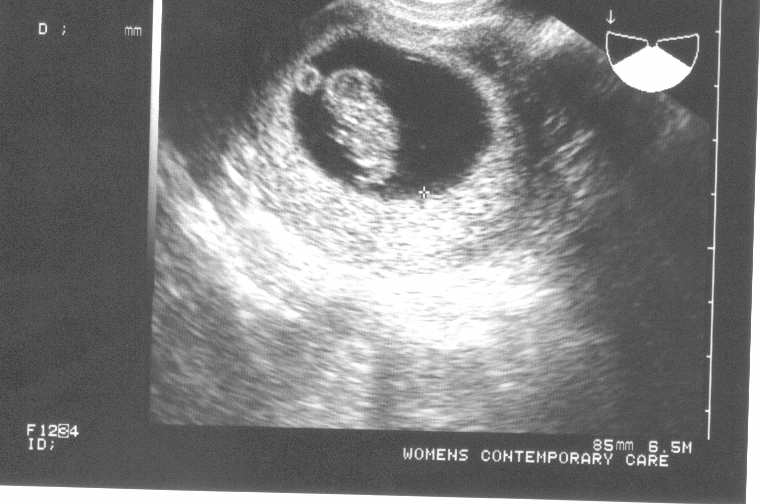

we saw the BABY today!!

we had our first appt today..

although we didnt get to hear the babys heartbeart we saw it beating!!

the legs and arms were moving and everything!! it was bigger than i thought it might be.

we are going for another sonogram and she said we will get a better picture!

Image Attachment(s):